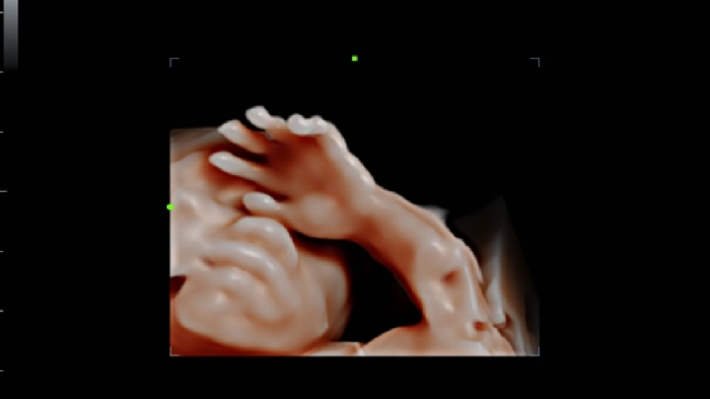

УЗИ-аппарат Mindray DC-70 — это современная ультразвуковая система экспертного класса, предназначенная для проведения диагностических исследований в различных областях медицины, включая кардиологию, акушерство и гинекологию, абдоминальные и сосудистые исследования. Аппарат сочетает высокое качество изображения с широким набором функциональных возможностей, что делает его эффективным инструментом для диагностики.

• Многофункциональность: Поддержка различных режимов сканирования, включая 2D, 3D/4D, цветное допплеровское картирование и другие, позволяет использовать аппарат для широкого спектра медицинских задач;

• iLive™ — технология 3D/4D-визуализации с функцией постобработки изображений;

Изображения